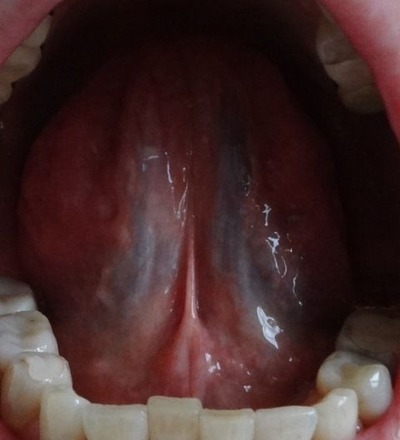

【2013年8月7日 漢方薬服用前の舌の裏】

舌の根本に黒々しい膨らみが見えます

この場合 舌を上にあげて1〜2分しますと

より一層黒い静脈血管が見えてきます

早く写真を撮りすぎて黒さが出ていません

若しくは皮膚が乾燥していますと 筋が硬く

舌を上に大きく上げられない 口を大きく開けられない場合があります

【2013年8月30日 漢方薬服用22日後の舌の裏】

筋が潤い柔らかくなりますと舌も柔軟になり上にしっかりあげられるようになります

静脈血管に黒い部分は於血毒素 炎症 火です

黒い色は於血 毒素 火 炎症 です。